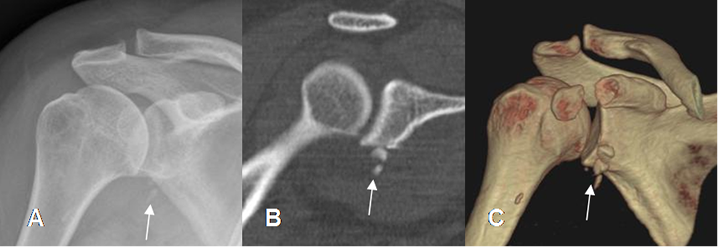

Fig 47. Luxación anterior.

A: Rx AP, B: TAC reconstrucción coronal y C: TAC reconstrucción 3D. Hombro reducido después de una luxación anterior, donde se identifican fragmentos óseos por debajo de la glenoides, por fractura.